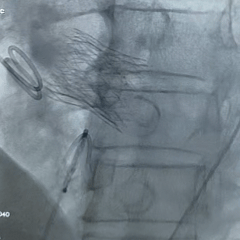

手术过程

根部造影:可见瓣叶钙化,几乎无反流

20mm球囊扩张,无腰,球囊轻微滑动

瓣膜系统定位

瓣膜展开后造影评估,深度可,无明显瓣周漏

多角度造影评估:瓣膜深度形态合适,冠脉灌注良好

脱钩后造影:瓣膜无位移,同轴性良好,无瓣周漏

术后超声测量

即刻瓣口流速2.2m/s;平均压差9mmHg,手术结束